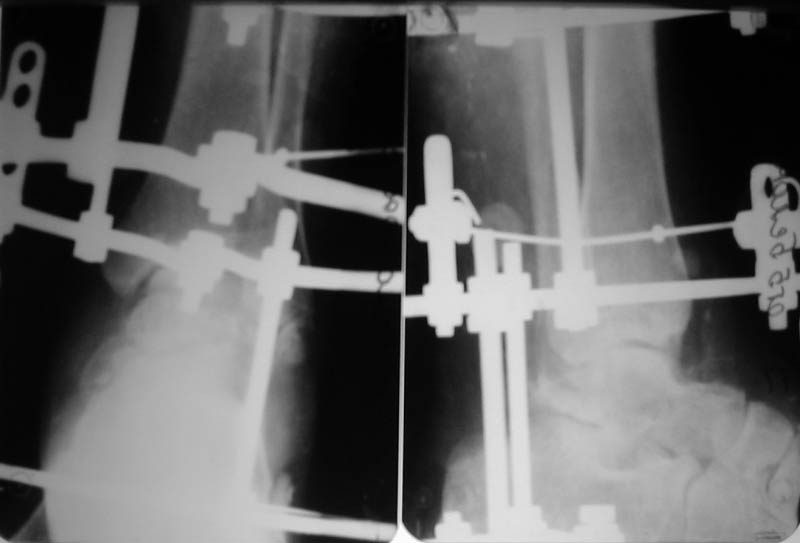

Что сделали. Под наркозом попытка закрытой ручной репозиции - безуспешно. Латеральный доступ, открытая репозиция таранной кости. Наложение АВФ (2 кольца, 2 полукольца на пятке и переднем отделе стопы). Устранение подтаранного вывиха стопы. Послеоперационные снимки в приложении.

Рекомендованную медикаментозную терапию получает. Баротерапия. По поводу повторной операции - пока нет особых мнений.

Оценка проведенного лечения?

Фото послеоперационых снимков немного не в фокусе еще к тому же.